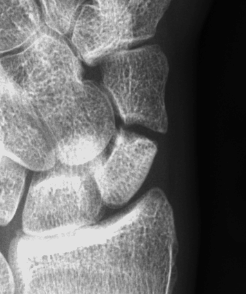

Scaphoid waist fracture 1 mm displaced

Scaphoid fracture with significant displacement

Scaphoid proximal pole fracture